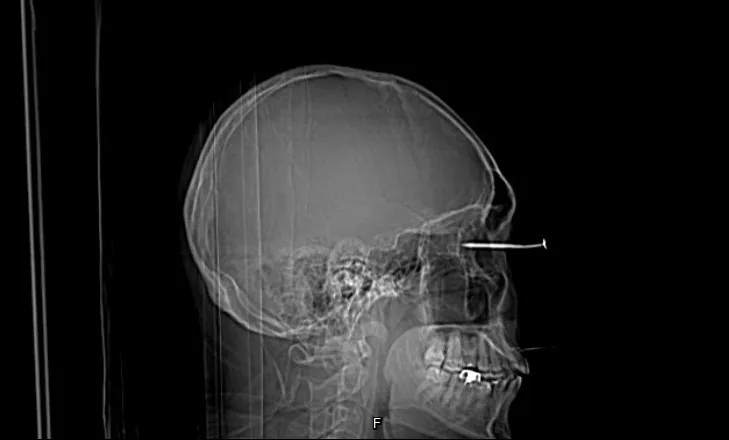

電腦斷層影像可看到男子右眼插著一根釘子,直達眼球的後方。李學宇醫師提供